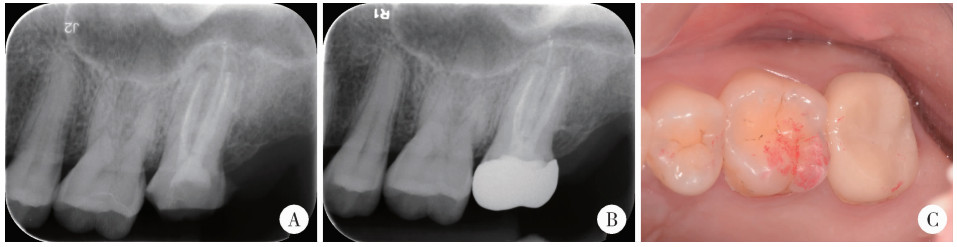

Figure 3

Follow-up periapical radiographs and intraoral photograph of left maxillary second molar A, 3-month follow-up shows initial healing of the periapical lesion; B, C, 10-month periapical and clinical evaluation shows a favorable prognosis."